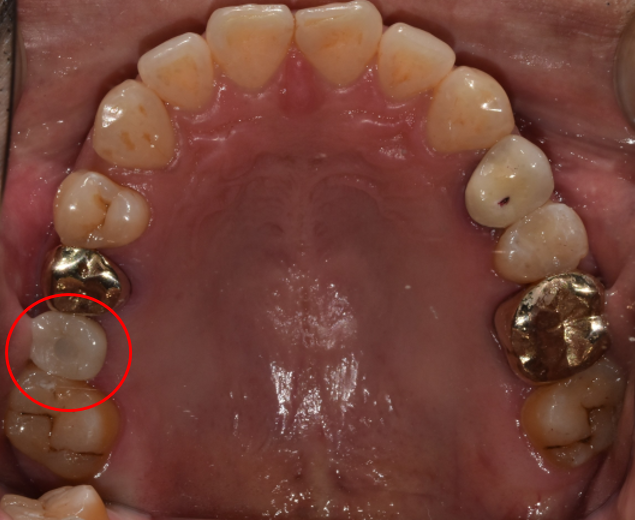

치료 전 : BRFORE

청담역치과 2021-07-22

치료 전 사진입니다.

십 년 전, 딱딱한 음식을 먹다가 치아가 상실하였다고 합니다.

그동안은 크게 불편하지 않아 빠진 것도 잊고 지냈는데

양옆의 치아가 점점 비어있는 공간으로 기울고 있다는 느낌이 들고 음식물을 씹을 때도 점점 불편하셨다고 합니다.

"법 먹는 게 불편하다 보니 괴로워지네요. 하루빨리 마음 편안하게 밥을 먹고 싶습니다."라고 말씀하셔서 그동안 많이 불편했음을 짐작하며 안타까운 마음뿐이었습니다.